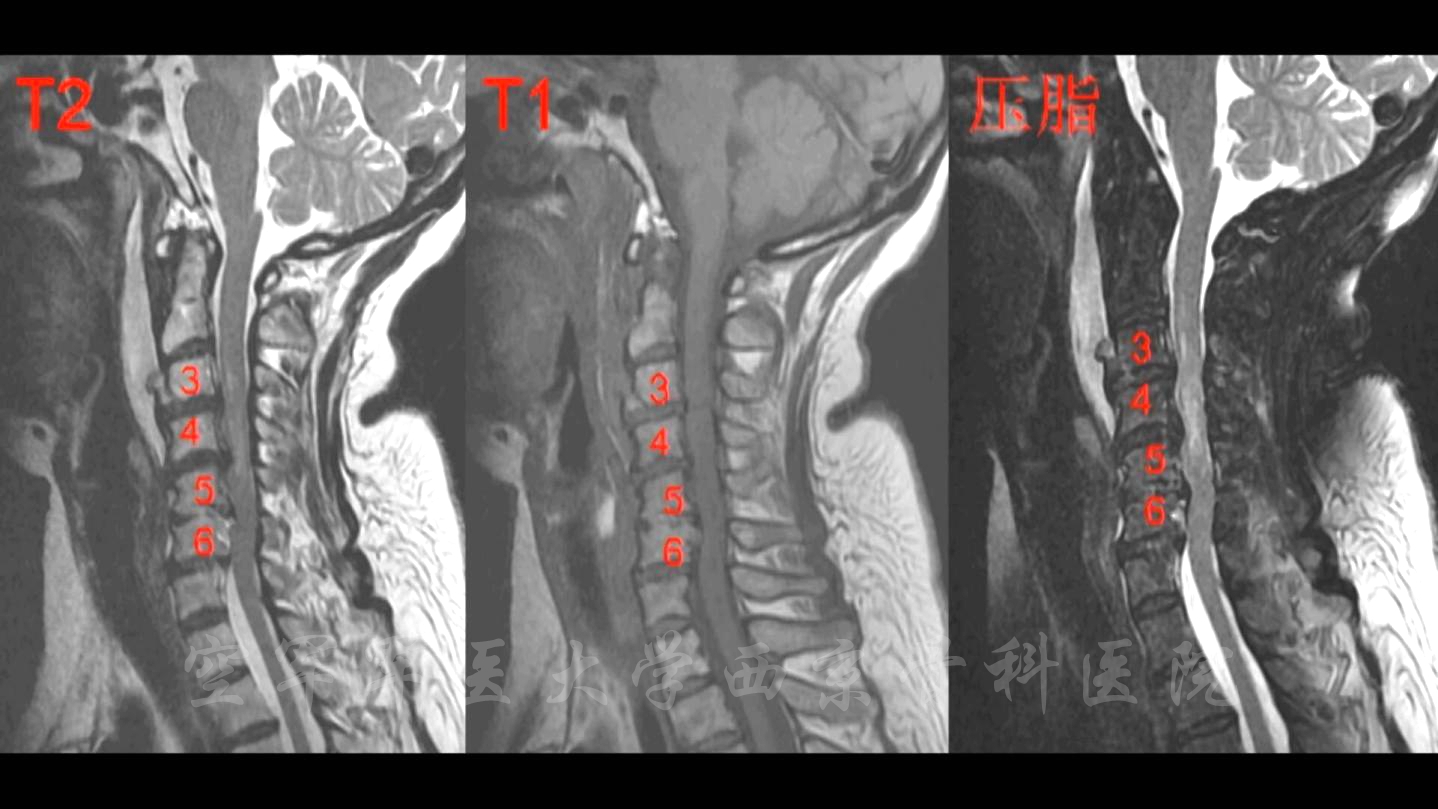

术前MRI